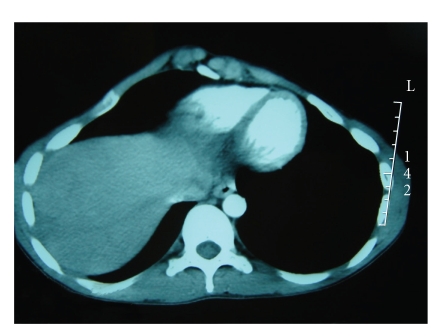

A second tomography done one month later described the same lesion with the same characteristics but with a dramatic decrease in size which is evaluated to be 2 cm in diameter (Figure 4). This spontaneous regression in size associated with radiological characteristics of a partially fibrous lesion permitted us to make the diagnosis of IPL and to abstain from any therapeutics. The patient is doing well and another radiologic control is foreseen in 6 months.

Figure 4.

CT scan showing a decrease in tumor size which is evaluated to be 2 cm.